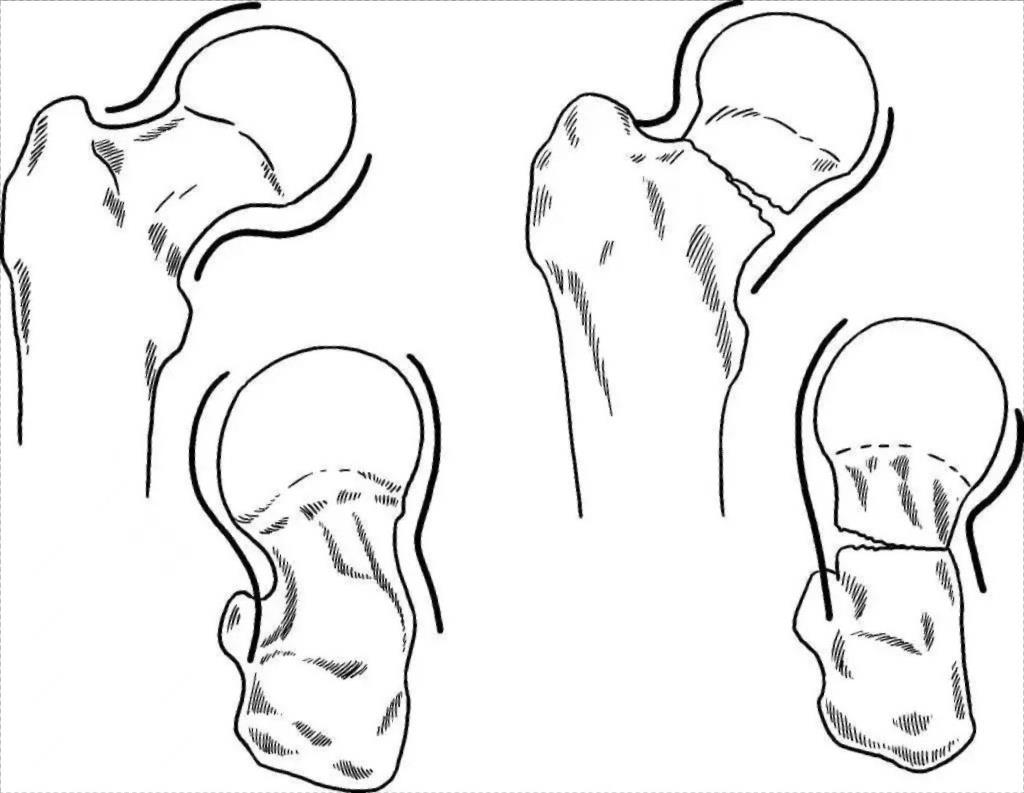

Figure 5 Manipulation du segment de fracture proximal pour un repositionnement fermé à l'aide de la tige de repositionnement intramédullaire

Figure 6 Réduction fermée à l'aide d'un clou de Schanz placé dans la corticale osseuse unilatérale à l'extrémité de la fracture

Figure 7 Fixation par clou centromédullaire à réduction fermée d'une fracture comminutive multisegmentaire de la tige fémorale à l'aide du clou de Schanz